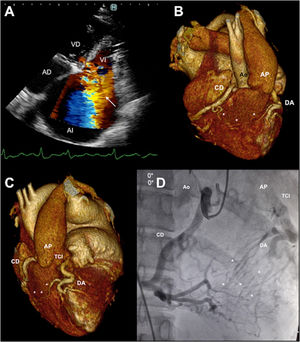

En el ecocardiograma se observó insuficiencia mitral grave (fig. 1 A, flecha. AD: aurícula derecha; AI: aurícula izquierda; VD: ventrículo derecho; VI: ventrículo izquierdo), dilatación grave de la AI y leve del VI con fracción de eyección del 55%.

La angiotomografía computarizada de arterias coronarias mostró una coronaria derecha muy desarrollada que nace del seno coronario derecho, origen anómalo de la arteria coronaria izquierda del tronco de la arteria pulmonar (ALCAPA) (fig. 1B,C. Ao: aorta; AP: arteria pulmonar; CD: arteria coronaria derecha; DA: arteria descendente anterior; TCI: tronco coronario izquierdo) con circulación colateral entre ambas coronarias (fig. 1B,C, asteriscos) y dilatación de la AP. La coronariografía confirmó el significativo flujo colateral intercoronariano, y mostró flujo retrógrado desde el TCI hacia la AP (fig. 1D).